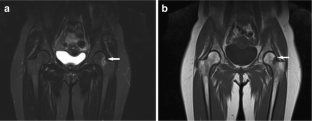

Incidental findings other than scoliosis were recorded in 104/247 (42%) patients, most often affecting the musculoskeletal system (65/247 patients, 26%). We found 16/247 (6.5%) significant incidental findings likely to affect clinical management, including avascular necrosis of bone in eight patients (five with NF2), eight insufficiency fractures, and four non-neurogenic neoplasms (Hodgkin's lymphoma, liposarcoma, dermoid cyst, large uterine myoma requiring excision). Scoliosis was seen in 50/247 patients (20%), including 8/55 with NF2 (15%) and 11/51 with schwannomatosis (22%).

Incidental findings in the neurofibromatoses frequently involve the skeleton. Given the relatively high incidence of unsuspected osteonecrosis and stress fractures, close attention to the skeleton on WBMRI is advised. In addition, knowledge of common incidental findings can help clinicians prepare patients who undergo WBMRI for potential unexpected findings.